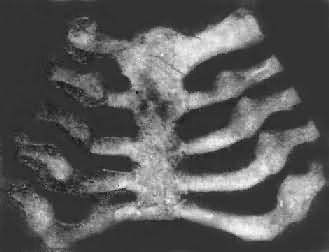

佝偻病的肋骨

图17-11 佝偻病的肋骨

肋骨和肋软骨结合部呈结节状隆起,排列成行,形似串珠